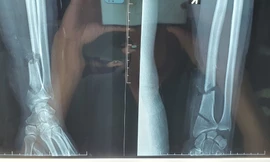

TPO - Trong lúc dùng máy cưa cầm tay để tỉa cây cảnh, một người đàn ông bất ngờ cắt trúng thân cây quá cứng, vô tình máy bị dội ra khiến cổ tay phải bị cắt trúng đứt gần lìa 2 đoạn. Sau đó, chiếc máy rớt còn xuống đất trúng cổ chân 2 bên, bệnh nhân phải nhập viện trong tình trạng vô cùng nguy kịch.

Sau pha vào bóng của Vũ Anh Tuấn, tiền đạo Alaan Bruno của Than Quảng Ninh đổ gục xuống sân kêu gào thảm thiết, với chiếc cổ chân bị gãy lệch sang một bên.

TP - Chấn thương ở cổ chân phải Văn Quyến, được phát hiện trong thời gian tập trung đội tuyển chuẩn bị cho AFF cup cuối năm ngoái đang có dấu hiệu tái phát. Theo chẩn đoán ban đầu của các bác sỹ, có thể vết thương đã bị tràn dịch.